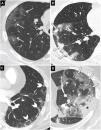

Figura 6.Hallazgos típicos de neumonía COVID-19 en tomografía computarizada (TC). Imágenes axiales de TC de tórax con cortes de 1mm. A) Opacidades en vidrio deslustrado de morfología redondeada y distribución periférica y subpleural (flechas). B) Consolidaciones de predominio periférico y subpleural (flechas). C) Reticulación de localización periférica y subpleural (puntas de flecha). D) Opacidades en vidrio deslustrado periféricas con engrosamiento de septos inter- e intralobulillares superpuesto en relación con patrón en empedrado (flecha). Se observa además una consolidación periférica (asterisco).

- •

Consolidación (fig. 6B): consiste en un aumento de la atenuación pulmonar que borra los vasos y las paredes de la vía aérea. Es el segundo patrón por frecuencia, aparecen asociadas al vidrio deslustrado (44%) y menos frecuentemente solas (24%)51. Indica progresión de la enfermedad.

Reticulación periférica (fig. 6C) por engrosamiento de los septos inter- e intralobulillares. Aumenta con el curso prolongado de la enfermedad51.

Patrón en empedrado (fig. 6D): patrón lineal por engrosamiento de septos interlobulillares que se superpone a un patrón en vidrio deslustrado subyacente. Se debe a edema alveolar e inflamación intersticial aguda. Es un signo de progresión de la enfermedad50.

Otros signos menos frecuentes:

Signo del halo invertido (fig. 7A y B): representa una opacidad central en vidrio deslustrado rodeada de una consolidación en forma de media luna o anillo. No está claro si representa una mejoría de la consolidación o una progresión del vidrio deslustrado. Aunque no es un hallazgo frecuente, es considerado entre los hallazgos típicos41,50,52.

Figura 7.Hallazgos típicos de neumonía COVID-19 en tomografía computarizada (TC). Imágenes de TC de tórax con cortes de 1mm. A y B) Imágenes axial (A) y sagital (B) que muestran una lesión en el segmento posterior del lóbulo superior derecho con el signo del halo invertido (flechas). C) Extensa afectación en vidrio deslustrado con áreas de consolidación en lóbulo inferior derecho con el signo de la vacuola (puntas de flecha). D) Alteración de la arquitectura del lóbulo inferior derecho con patrón en empedrado y dilatación bronquial (flecha negra).

Signo de la burbuja de aire-vacuola (fig. 7C): se refiere a un pequeño espacio hipodenso pulmonar, menor de 5mm, en el interior de la opacidad en vidrio deslustrado; podría corresponder a la dilatación patológica de un espacio fisiológico, a la sección transversal de una bronquiolectasia o ser secundario a la resolución de las consolidaciones51.

Cambios en la vía aérea, con dilataciones bronquiales (fig. 7D) en las áreas de vidrio deslustrado y engrosamiento de la pared bronquial por inflamación.

Vasos prominentes: dilatación de los vasos pulmonares peri- o intralesionales (fig. 8A) por daño de la pared capilar en respuesta a factores inflamatorios50.